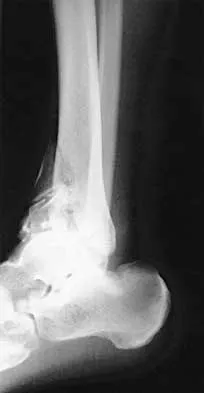

Figures 4a through 4c show the radiographs of a 43-year-old woman who sustained a twisting injury to her right ankle. She has ankle pain and tenderness medially and laterally. To help determine the optimal treatment, an external rotation stress radiograph of the ankle is obtained. This test is designed to evaluate the integrity of what structure?

Explanation

In the presence of a supination external rotation-type fracture of the distal fibula (Weber type B), stability of the ankle is best assessed by performing an external rotation stress AP view of the ankle. This test is used to assess the integrity of the deltoid ligament. The presence of a deltoid ligament rupture results in instability and generally is best managed surgically. The gravity stress test can also be used. Egol KA, Amirtharajah M, Tejwani NC, et al: Ankle stress test for predicting the need for surgical fixation of isolated fibular fractures. J Bone Joint Surg Am 2004;86:2393-2398. McConnell T, Creevy W, Tornetta P III: Stress examination of supination external rotation-type fibular fractures. J Bone Joint Surg Am 2004;86:2171-2178.